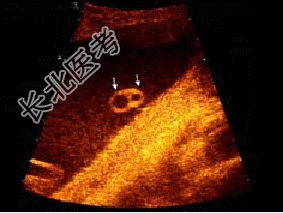

- 单项选择题如图,为一孕妇34W时, 羊水内漂浮所见管道结构(横切),最可能诊断为( )

A、脊柱裂

B、淋巴管囊肿

C、单脐动脉

D、正常图象

E、脑膜膨出